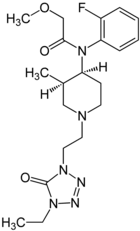

Anilidopiperidines

- 3-Allylfentanyl

- 3-Methylfentanyl

- 3-Methylthiofentanyl

- 4-Phenylfentanyl

- Alfentanil

- α-Methylacetylfentanyl

- α-Methylfentanyl

- α-Methylthiofentanyl

- Benzylfentanyl

- β-hydroxyfentanyl

- β-hydroxythiofentanyl

- β-Methylfentanyl

- Brifentanil

- Butyrfentanyl

- Carfentanil

- Fentanyl

- Lofentanil

- N-Methylcarfentanil

- Mirfentanil

- Ocfentanil

- Ohmefentanyl

- Parafluorofentanyl

- Phenaridine

- R-30490

- Remifentanil

- Sufentanil

- Thenylfentanyl

- Thiofentanyl

- Trefentanil

Structures